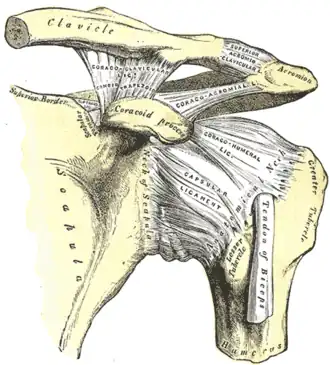

The left shoulder and acromioclavicular joints, and the proper ligaments of the scapula.

The left shoulder and acromioclavicular joints, and the proper ligaments of the scapula. -

The head (caput humeri) is nearly hemispherical in form. It is directed upward, medialward, and a little backward, and articulates with the glenoid cavity of the scapula to form the glenohumeral joint (shoulder joint). The circumference of its articular surface is slightly constricted and is termed the anatomical neck, in contradistinction to a constriction below the tubercles called the surgical neck which is frequently the seat of fracture. Fracture of the anatomical neck rarely occurs.[2] The diameter of the humeral head is generally larger in men than in women.

At the shoulder, the head of the humerus articulates with the glenoid fossa of the scapula. More distally, at the elbow, the capitulum of the humerus articulates with the head of the radius, and the trochlea of the humerus articulates with the trochlear notch of the ulna.